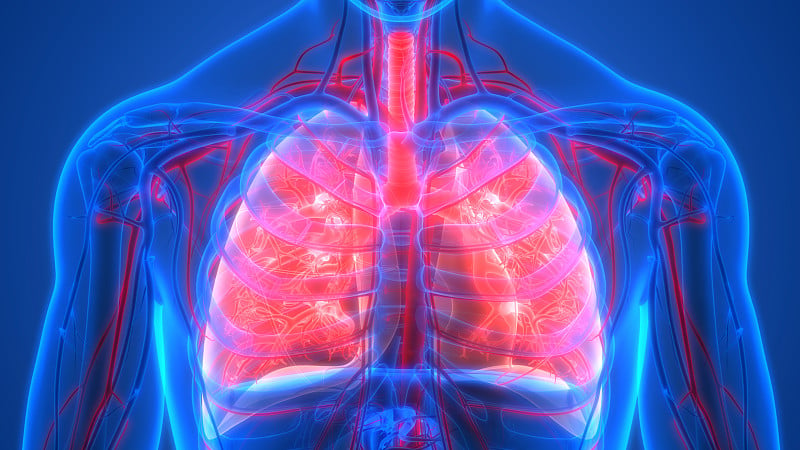

人体呼吸系统肺解剖学详情

人体呼吸系统肺解剖详情

人体呼吸系统肺解剖详情

人体呼吸系统肺解剖详情

人体呼吸系统肺解剖学详情

人体呼吸系统肺解剖学详情

人体呼吸系统肺解剖学详情

人体呼吸系统肺解剖详情

人体呼吸系统肺解剖学详情

人体呼吸系统肺解剖学详情

人体呼吸系统肺解剖详情

人体呼吸系统肺解剖详情

人体呼吸系统肺解剖详情